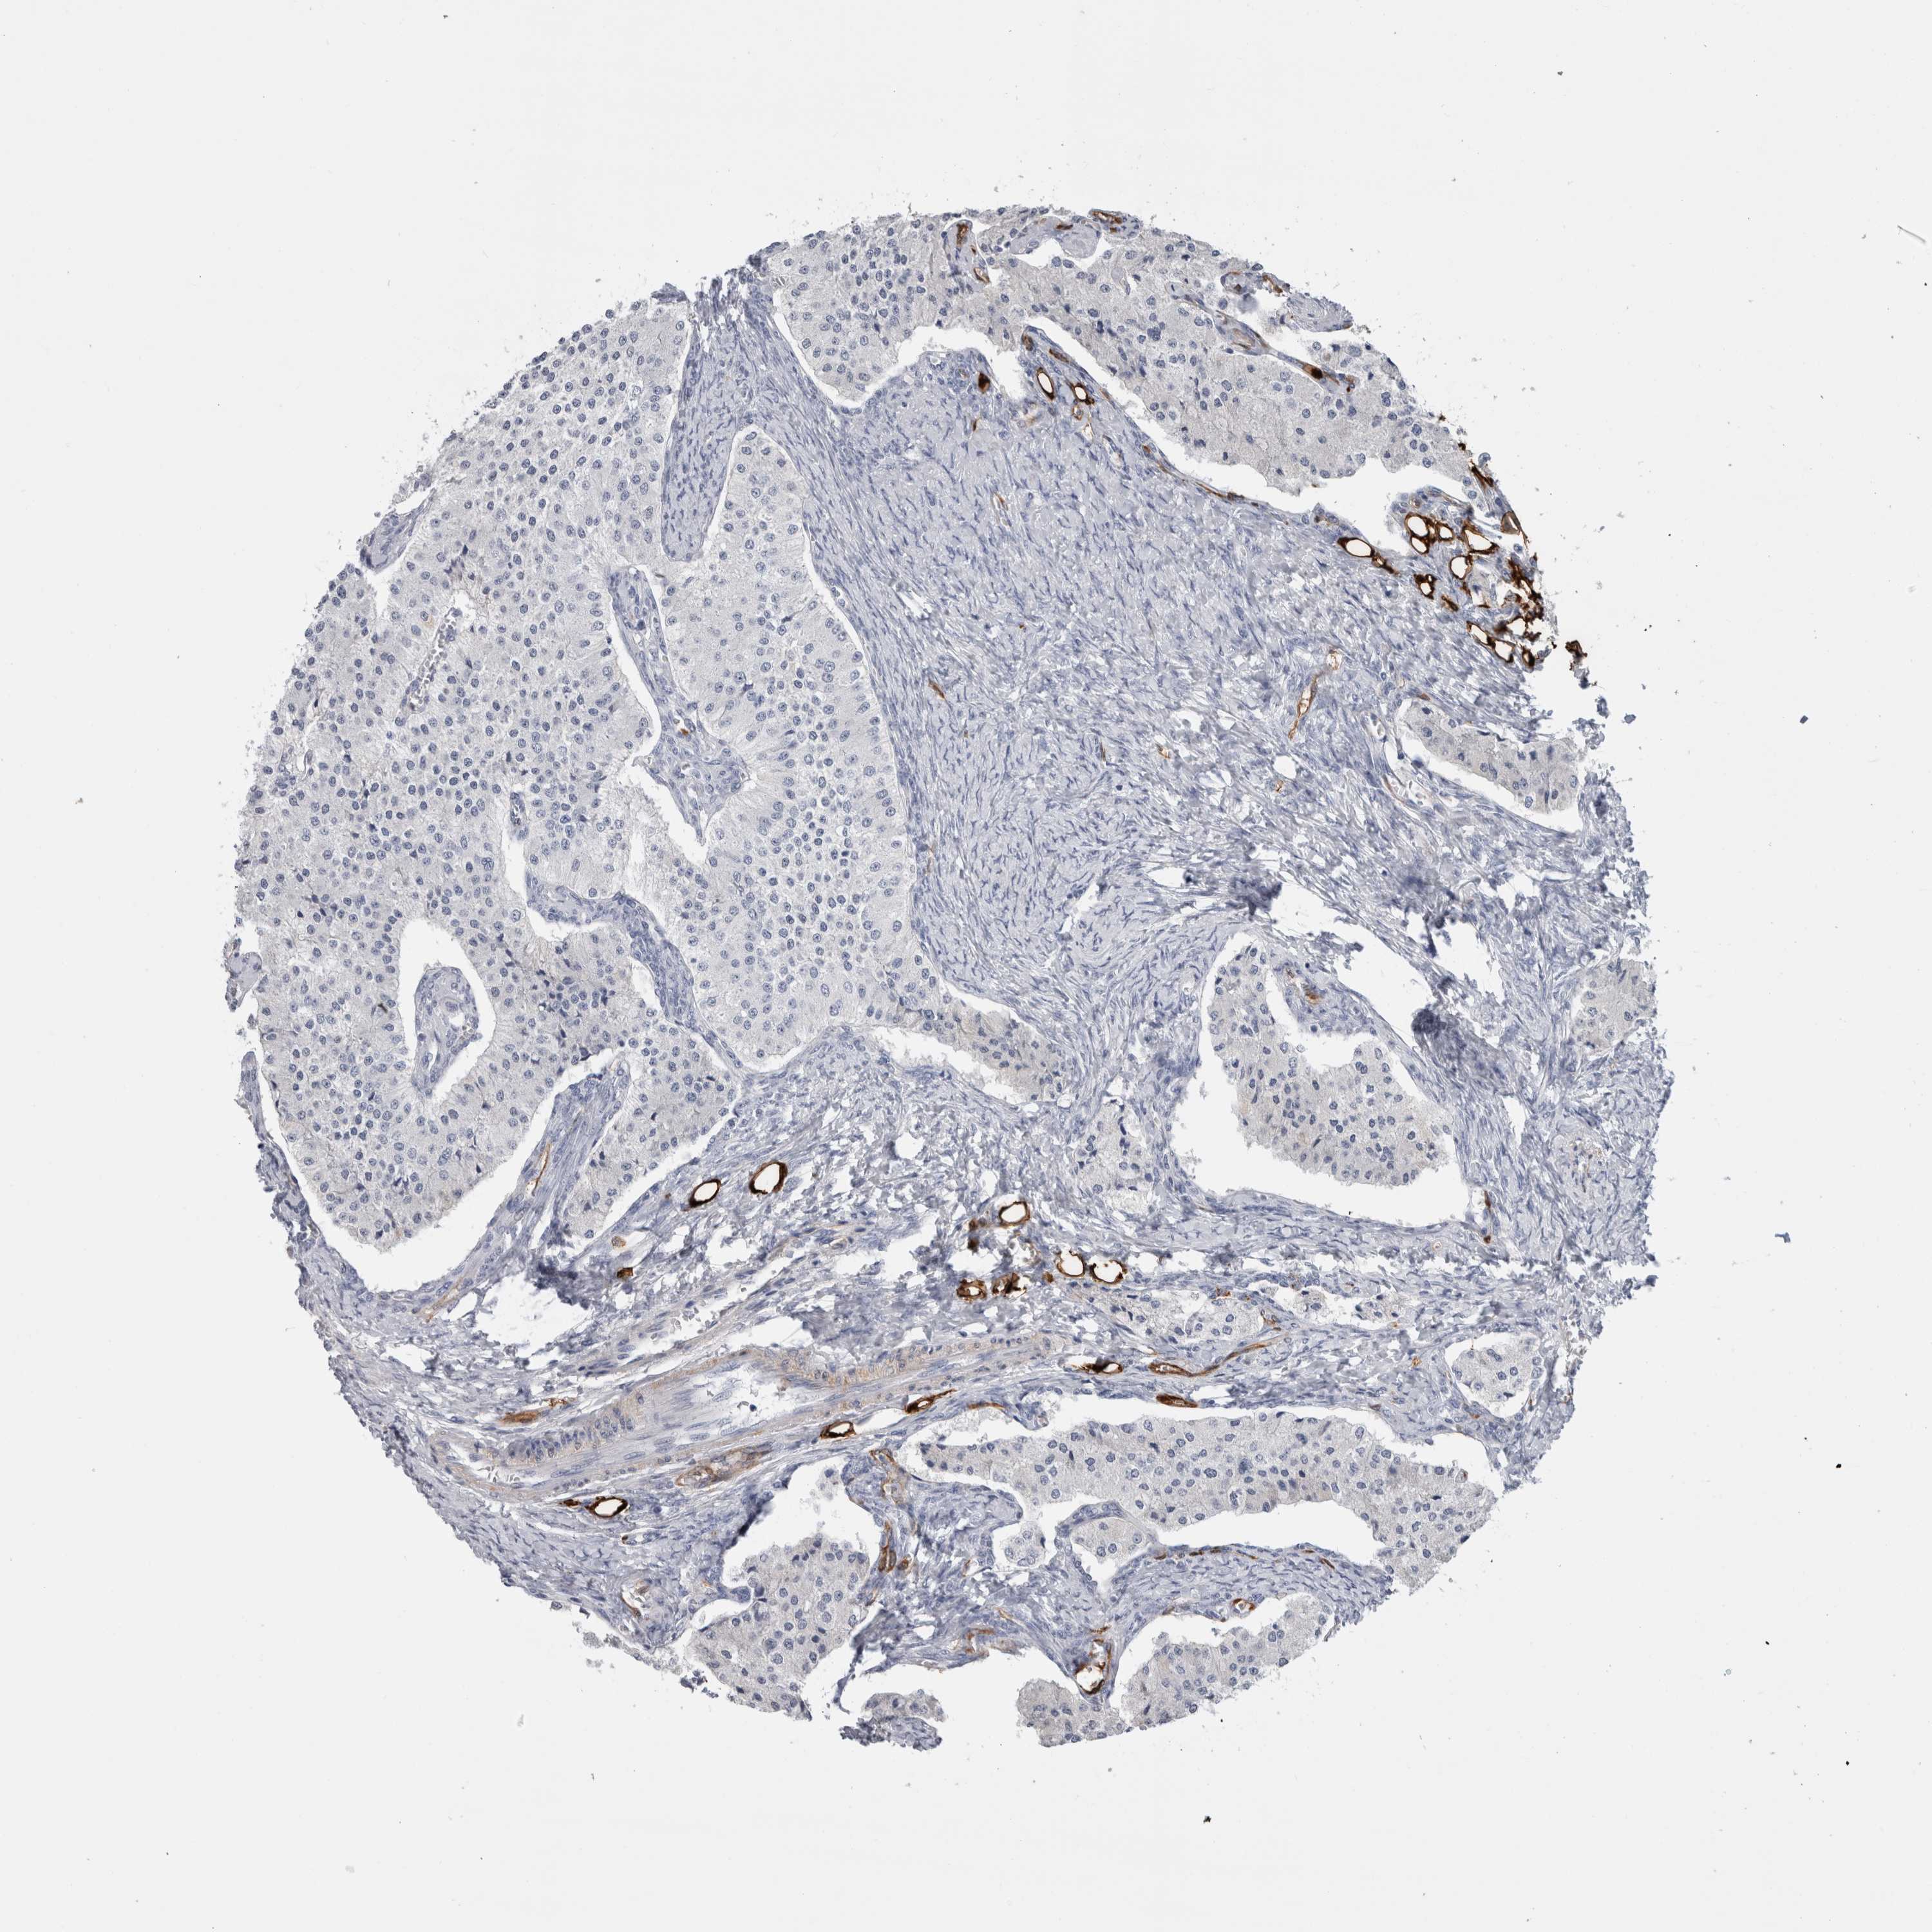

FABP4